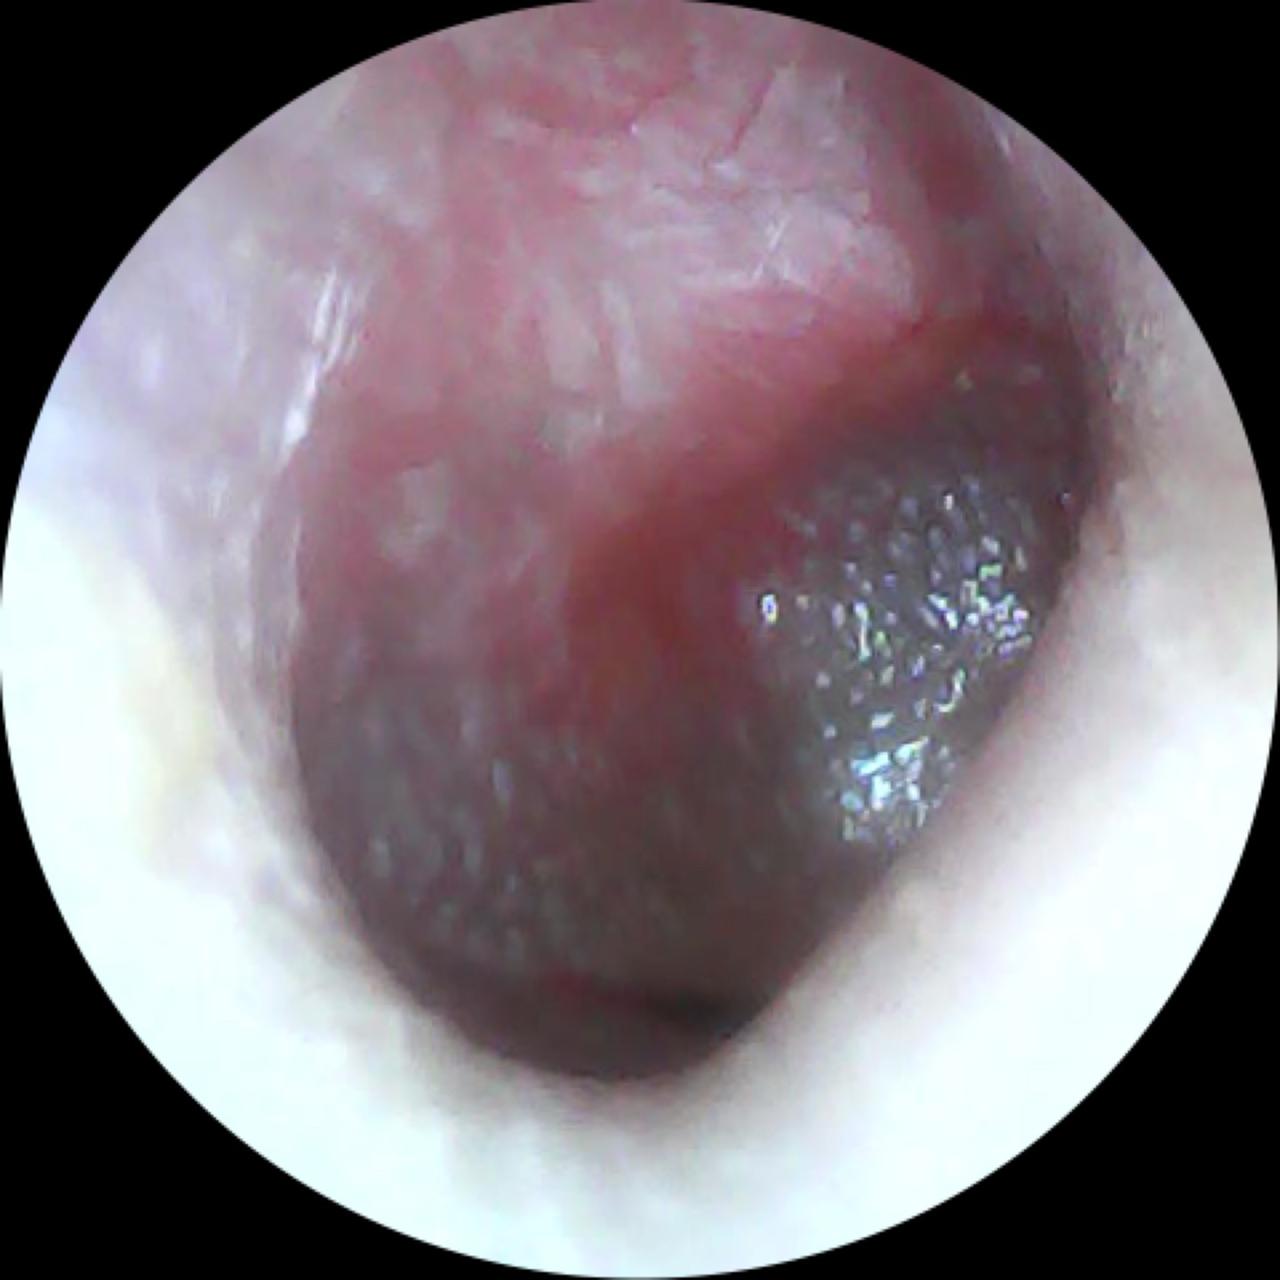

A otite média aguda é um processo inflamatório da orelha média, geralmente causado por infecções virais ou bacterianas. Ocorre quando a tuba auditiva, canal que liga a orelha média à garganta, fica bloqueada, dificultando a drenagem do muco. O resultado é o acúmulo de líquido e pus, provocando dor intensa e outros sintomas desconfortáveis. O Dr. Carlos Rezende destaca que os principais sintomas incluem dor de ouvido, febre e, possivelmente, a saída de secreção. Normalmente, a otite média aguda acompanha quadros gripais.

Os sintomas mais comuns incluem dor intensa na orelha, febre (especialmente em crianças), sensação de orelha tampada, perda auditiva temporária, e secreção em caso de perfuração do tímpano. No entanto, é importante saber diferenciar a otite média aguda de outras infecções de ouvido. O Dr. Carlos destaca que a otite média aguda é geralmente acompanhada por febre e dor, enquanto a otite média com efusão se caracteriza principalmente por redução da audição e sensação de abafamento auditivo. Além disso, a otite externa costuma causar dor, mas raramente febre, e geralmente está relacionada à manipulação do canal auditivo, como o uso frequente de hastes flexíveis.

O diagnóstico de otite média aguda é clínico, baseado na anamnese e no exame físico. O Dr. Carlos destaca que, hoje, há um grande avanço na ponderação sobre a necessidade de antibióticos, uma vez que muitos casos podem ser tratados com controle dos sintomas e monitoramento.